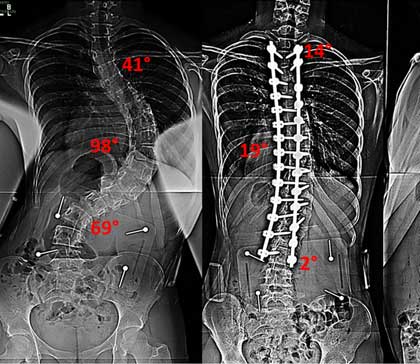

Minimally invasive scoliosis surgery is a type of procedure done to fix an abnormal curve of the spine known as scoliosis. This type of surgery uses smaller incisions than open surgery.

The spine has some normal curves forward and backward. But it should not curve to the side. With scoliosis, the spine curves to the side in an S-shape or a C-shape. If the curve is severe, it can cause uneven shoulders or a body that appears to tilt to one side.